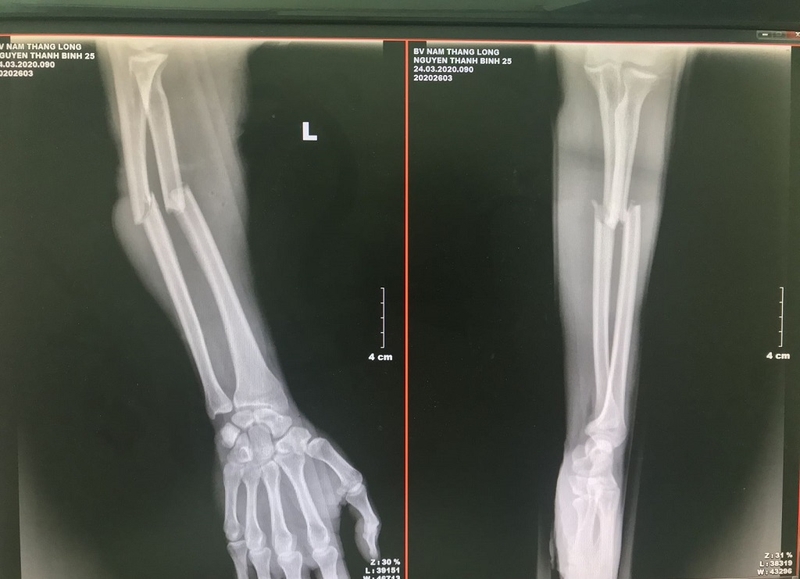

Sau khi thực hiện sơ cứu gãy xương kín và chuyển bệnh nhân đến bệnh viện, các bác sĩ sẽ thực hiện chụp X-quang, cắt lớp vi tính hoặc cộng hưởng từ để xem xét và chẩn đoán. Thông thường, người bệnh được chỉ định chụp X - quang.

Cách sơ cứu gãy xương kín như thế nào? Chụp X-quang dùng để chẩn đoán gãy xương kín